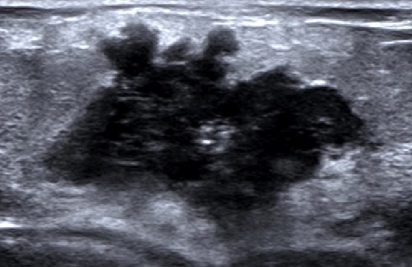

圖示:乳腺癌(邊界不清,形態(tài)不規(guī)則)

這是超聲最核心的作用。它能判斷摸到的腫塊是囊性(充滿液體的囊腫,通常為良性)還是實質(zhì)性(有實性結(jié)構(gòu)的包塊)。比如,一個邊界清晰、形態(tài)規(guī)則、內(nèi)部無血流的橢圓形腫塊,大概率是良性的;而一個邊界不清、形態(tài)不規(guī)則、內(nèi)有豐富血流信號的腫塊,則需警惕乳腺癌可能。